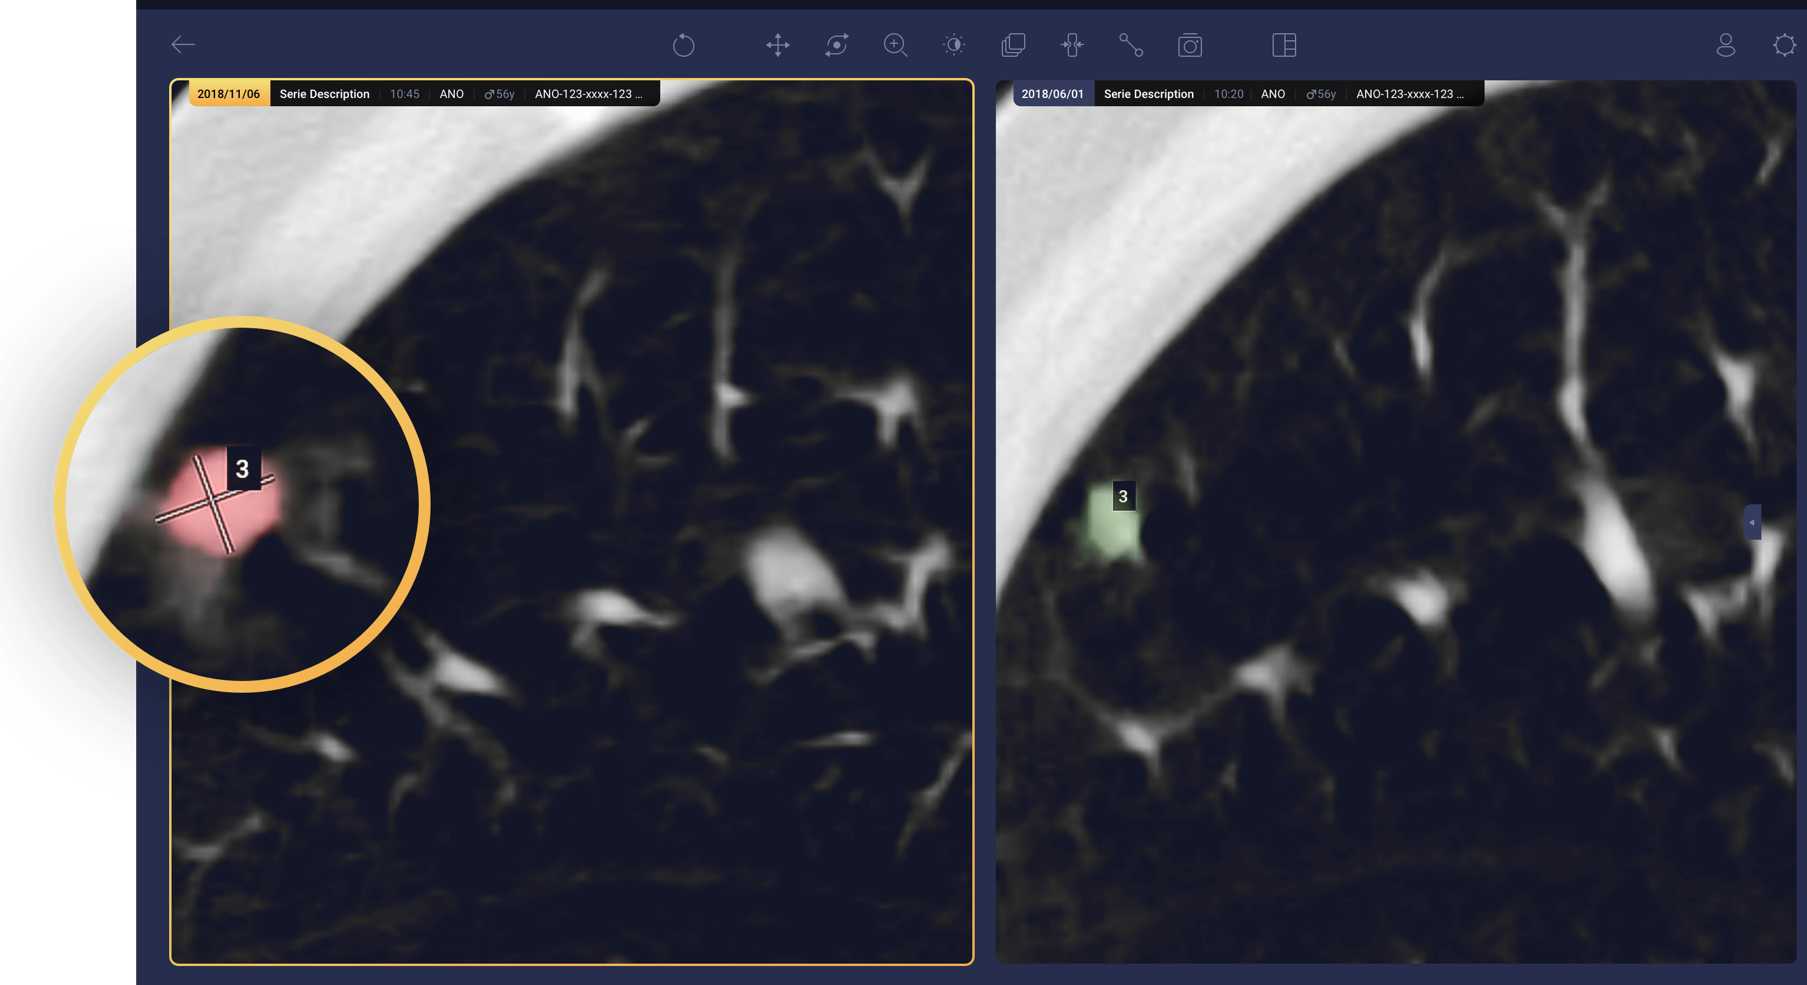

- Lung nodule detection, characterization, and radiomics